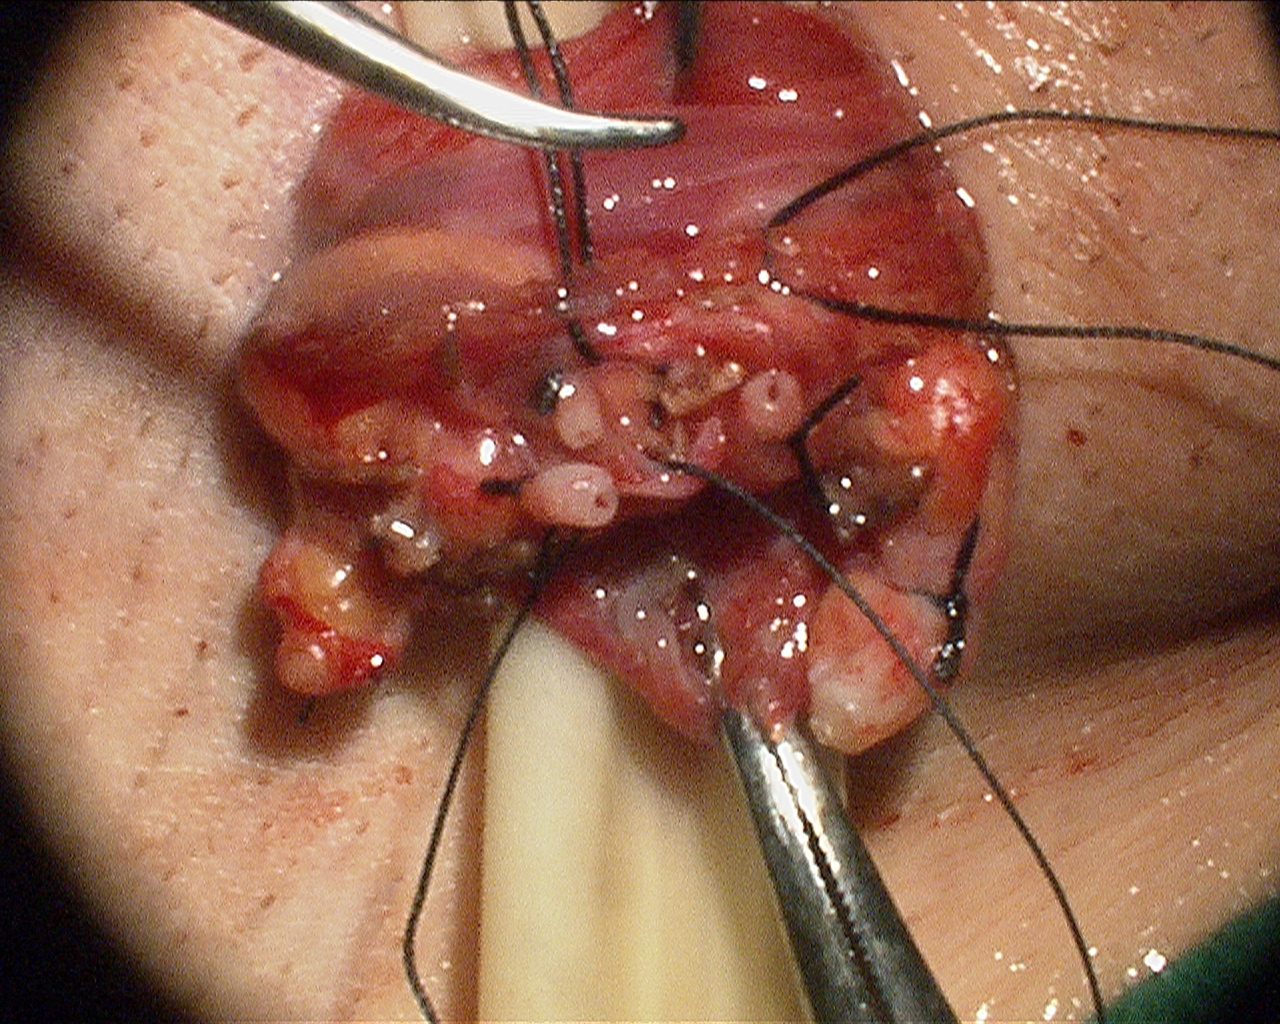

Today, however, we can offer patients Microsurgical Denervation of the Spermatc Cord (MDSC). This minimally-invasive procedure allows for relief of pain and preserves testicular function.

Prior to surgery, patients are given a nerve block in the office. If pain improves with the nerve block, then patients are offered MDSC.

While no procedure is 100% effective, up to 80-90% of patients report durable improvement and relief of their testicular pain.